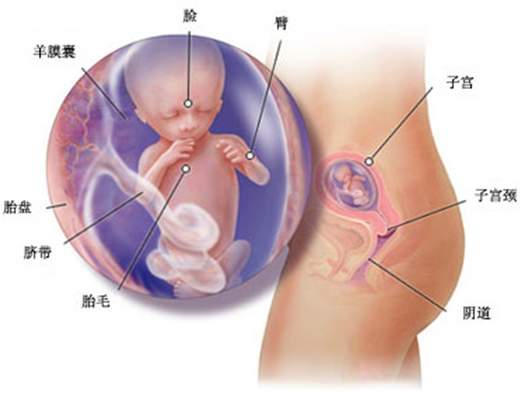

怀孕第 15 周胎儿发育情况

胎儿现在的生长速度很快,远远地超过了前几周,他(她)的身长已经达到 10-12 厘米,体重也达到 50 克。现在胎儿薄薄的皮肤上覆盖了一层细细的绒毛,全身看上去就像披着一层薄绒毯,这层绒毛通常出生时就会消失。

现在胎儿的眉毛开始长出来,头发也在头顶迅速生长,头发的纹理密度和颜色在出生后都会有所改变。胎儿在子宫里开始做许多动作,他(她)可以握紧拳头、眯着眼睛斜视、皱眉头、做鬼脸,也开始会吸吮自己的大拇指。研究者认为,这些动作会促进胎儿大脑的成长。